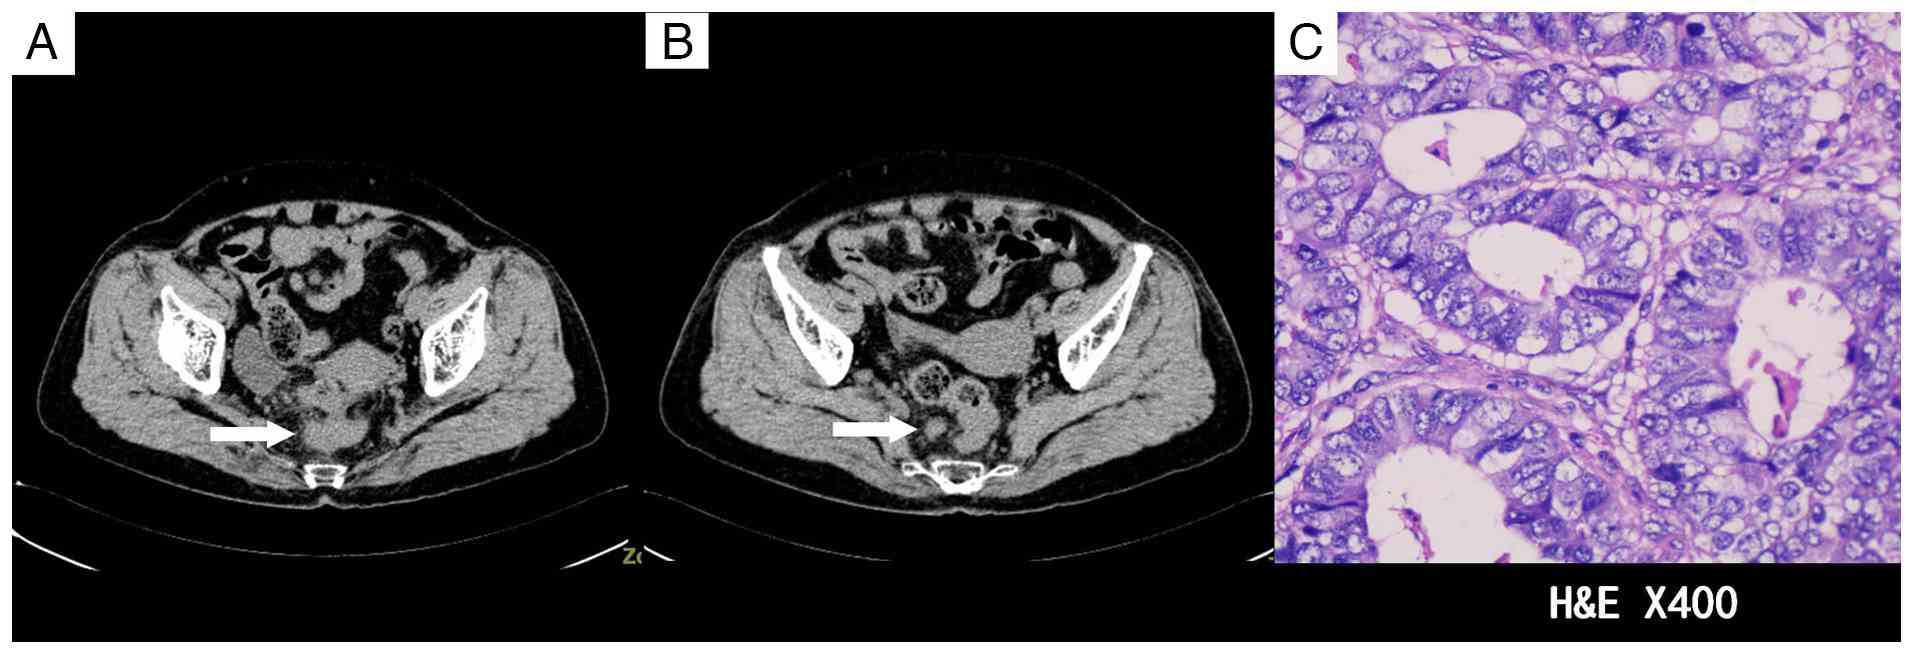

A total of 5 days after the initial chemotherapy treatment, the patient was admitted to the in the Department of Hepatobiliary Surgery and underwent RFA with a concurrent biopsy of the left hepatic lobe lesion. The postoperative pathology, performed as aforementioned, confirmed liver metastasis of colorectal cancer. The cells were arranged in irregular glandular structures with infiltrative growth, and the nuclei were enlarged, with prominent nucleoli (Fig. 3A). The patient developed abdominal pain and a fever following the operation. A CT scan 1 week after RFA revealed signs of infection (Fig. 3B and C), which recovered after antibiotic treatment. In October 2013, the chemotherapy regimen was switched to XELOX (1,500 mg capecitabine orally twice daily on days 1–14; 180 mg oxaliplatin by intravenous infusion on day 1), followed by TACE 8 days later, targeting the metastatic lesions in the right hepatic lobe. A contrast-enhanced CT scan conducted 10 days post-TACE showed no significant reduction in the size of the three lesions in the right hepatic lobe compared with the size in the images taken before the procedure, with persistent mild enhancement (Fig. 4).

Pathological and computed tomography

imaging in the left lobe of the liver following radiofrequency

ablation. (A) Histopathology of the lesion in the left lobe of the

liver reveals that the cells are arranged in irregular glandular

structures with infiltrative growth. The nuclei are enlarged and

nucleoli are prominent. The pathological diagnosis is metastatic

colorectal carcinoma to the liver. (B and C) A clustered

heterogeneous density shadow can be seen in the left lobe of the

liver, with gas density shadows within it (arrow). The adjacent

greater omentum is thickened. The results suggest infection.

Figure 3.

Pathological and computed tomography imaging in the left lobe of the liver following radiofrequency ablation. (A) Histopathology of the lesion in the left lobe of the liver reveals that the cells are arranged in irregular glandular structures with infiltrative growth. The nuclei are enlarged and nucleoli are prominent. The pathological diagnosis is metastatic colorectal carcinoma to the liver. (B and C) A clustered heterogeneous density shadow can be seen in the left lobe of the liver, with gas density shadows within it (arrow). The adjacent greater omentum is thickened. The results suggest infection.